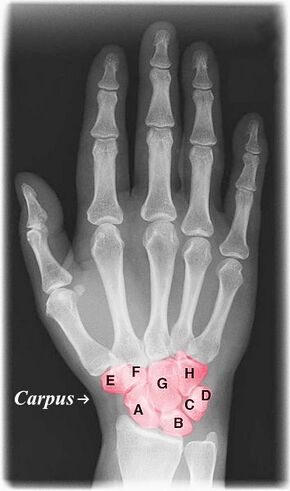

![]() Labelled image showing the eight carpal bones. | |

The carpal bones are the eight small bones that make up the wrist (carpus) that connects the hand to the forearm. The term "carpus" and "carpal" is derived from the Latin carpus and the Greek καρπός (karpós), meaning "wrist". In human anatomy, the main role of the carpal bones is to articulate with the radial and ulnar heads to form a highly mobile condyloid joint (i.e. wrist joint),[1] to provide attachments for thenar and hypothenar muscles, and to form part of the rigid carpal tunnel which allows the median nerve and tendons of the anterior forearm muscles to be transmitted to the hand and fingers.

The eight carpal bones may be conceptually organized as either two transverse rows, or three longitudinal columns.